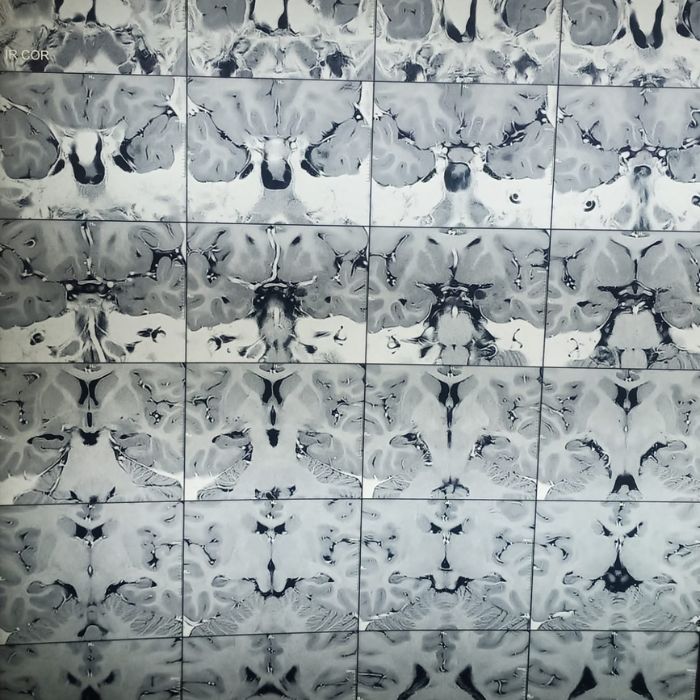

Tumor

Tumor begins when healthy cells in the brain or spinal cord change and grow out of control, forming a mass. A cancerous tumor spreads to other parts causing damage along its path. When the tumor is restricted to one location without causing significant damage it is said to be benign. The symptoms can be recurrent headaches, persistent vomiting, seizures, visual or hearing issues or even paralysis. Tumors are detected generally by imaging studies like MRI and CT scan. Further tests may be required to confirm the type, extent and to know if other body parts are involved. Treatment can be challenging at times and may require either medication, surgery, radiation or a combination.